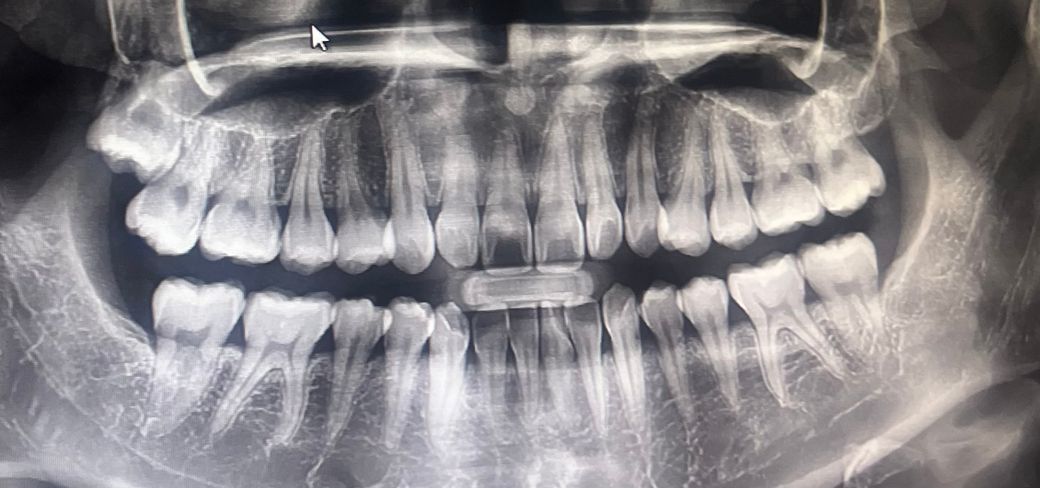

엑스레이상 치료가 급한 충치가 있나요 ?

오른쪽 위아래 어금니가 간헐적으로 시큰? 시려서 스케일링 갔다가 표면상 충치만 있는, 심하지는 않다고 하셔서 레진 치료만 받았는데요 증상이 별로 좋아지지도 않고...엑스레이상 인접면이나 뿌리쪽 충치가 없는게 정말 맞나요 ?

안녕하세요 치과의사 김철진입니다. 엑스레이 상으로는 충치가 심한건 보이진 않습니다. 지금처럼 관리 하시고 정기적으로 치과에 가셔서 체크를 받으세요.

• 특별히 오른쪽 위,아래로 눈에 보이는 충치는 없습니다. 다만 오른쪽 위의 경우 사랑니가 옆 어금니와 겹쳐 누르고 있는 양상입니다. 이런 경우 옆 어금니의 뿌리 흡수, 뿌리부위 충치가 야기될 수 있고 시린증상도 이와 관련될 수 있습니다.

• 파노라마 사진으로 봤을 경우에는 특별히 큰 충치가 없어 보입니다 하지만 정확한 확인은 육안으로 확인을 해야 하기 때문에 치과에서 진료를 받아 보는 것이 좋습니다.